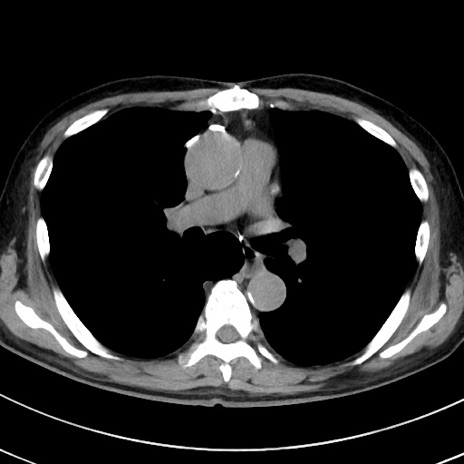

症例38(横断像)

【症例】70歳代 男性

【主訴】腹痛・嘔吐

【現病歴】昨晩より、嘔吐・腹痛あり。今朝になっても嘔吐あり。来院。

【既往歴】心臓バイパス手術、開腹胆摘、腸閉塞

【身体所見】BP 107/71mmHg、HR 116/min、腹部:平坦、軟、下腹部に軽度圧痛あり。反跳痛なし。

【データ】WBC 15100、CRP 0.32